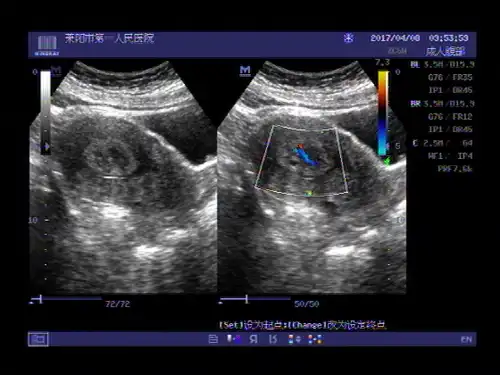

【原创】【资源】各种部位子宫肌瘤总结 - 超声医学讨论版 - 爱爱医

超声入门贴544看图请您会诊卵巢纤维瘤宫腔粘膜下肌瘤囊性变病理结果